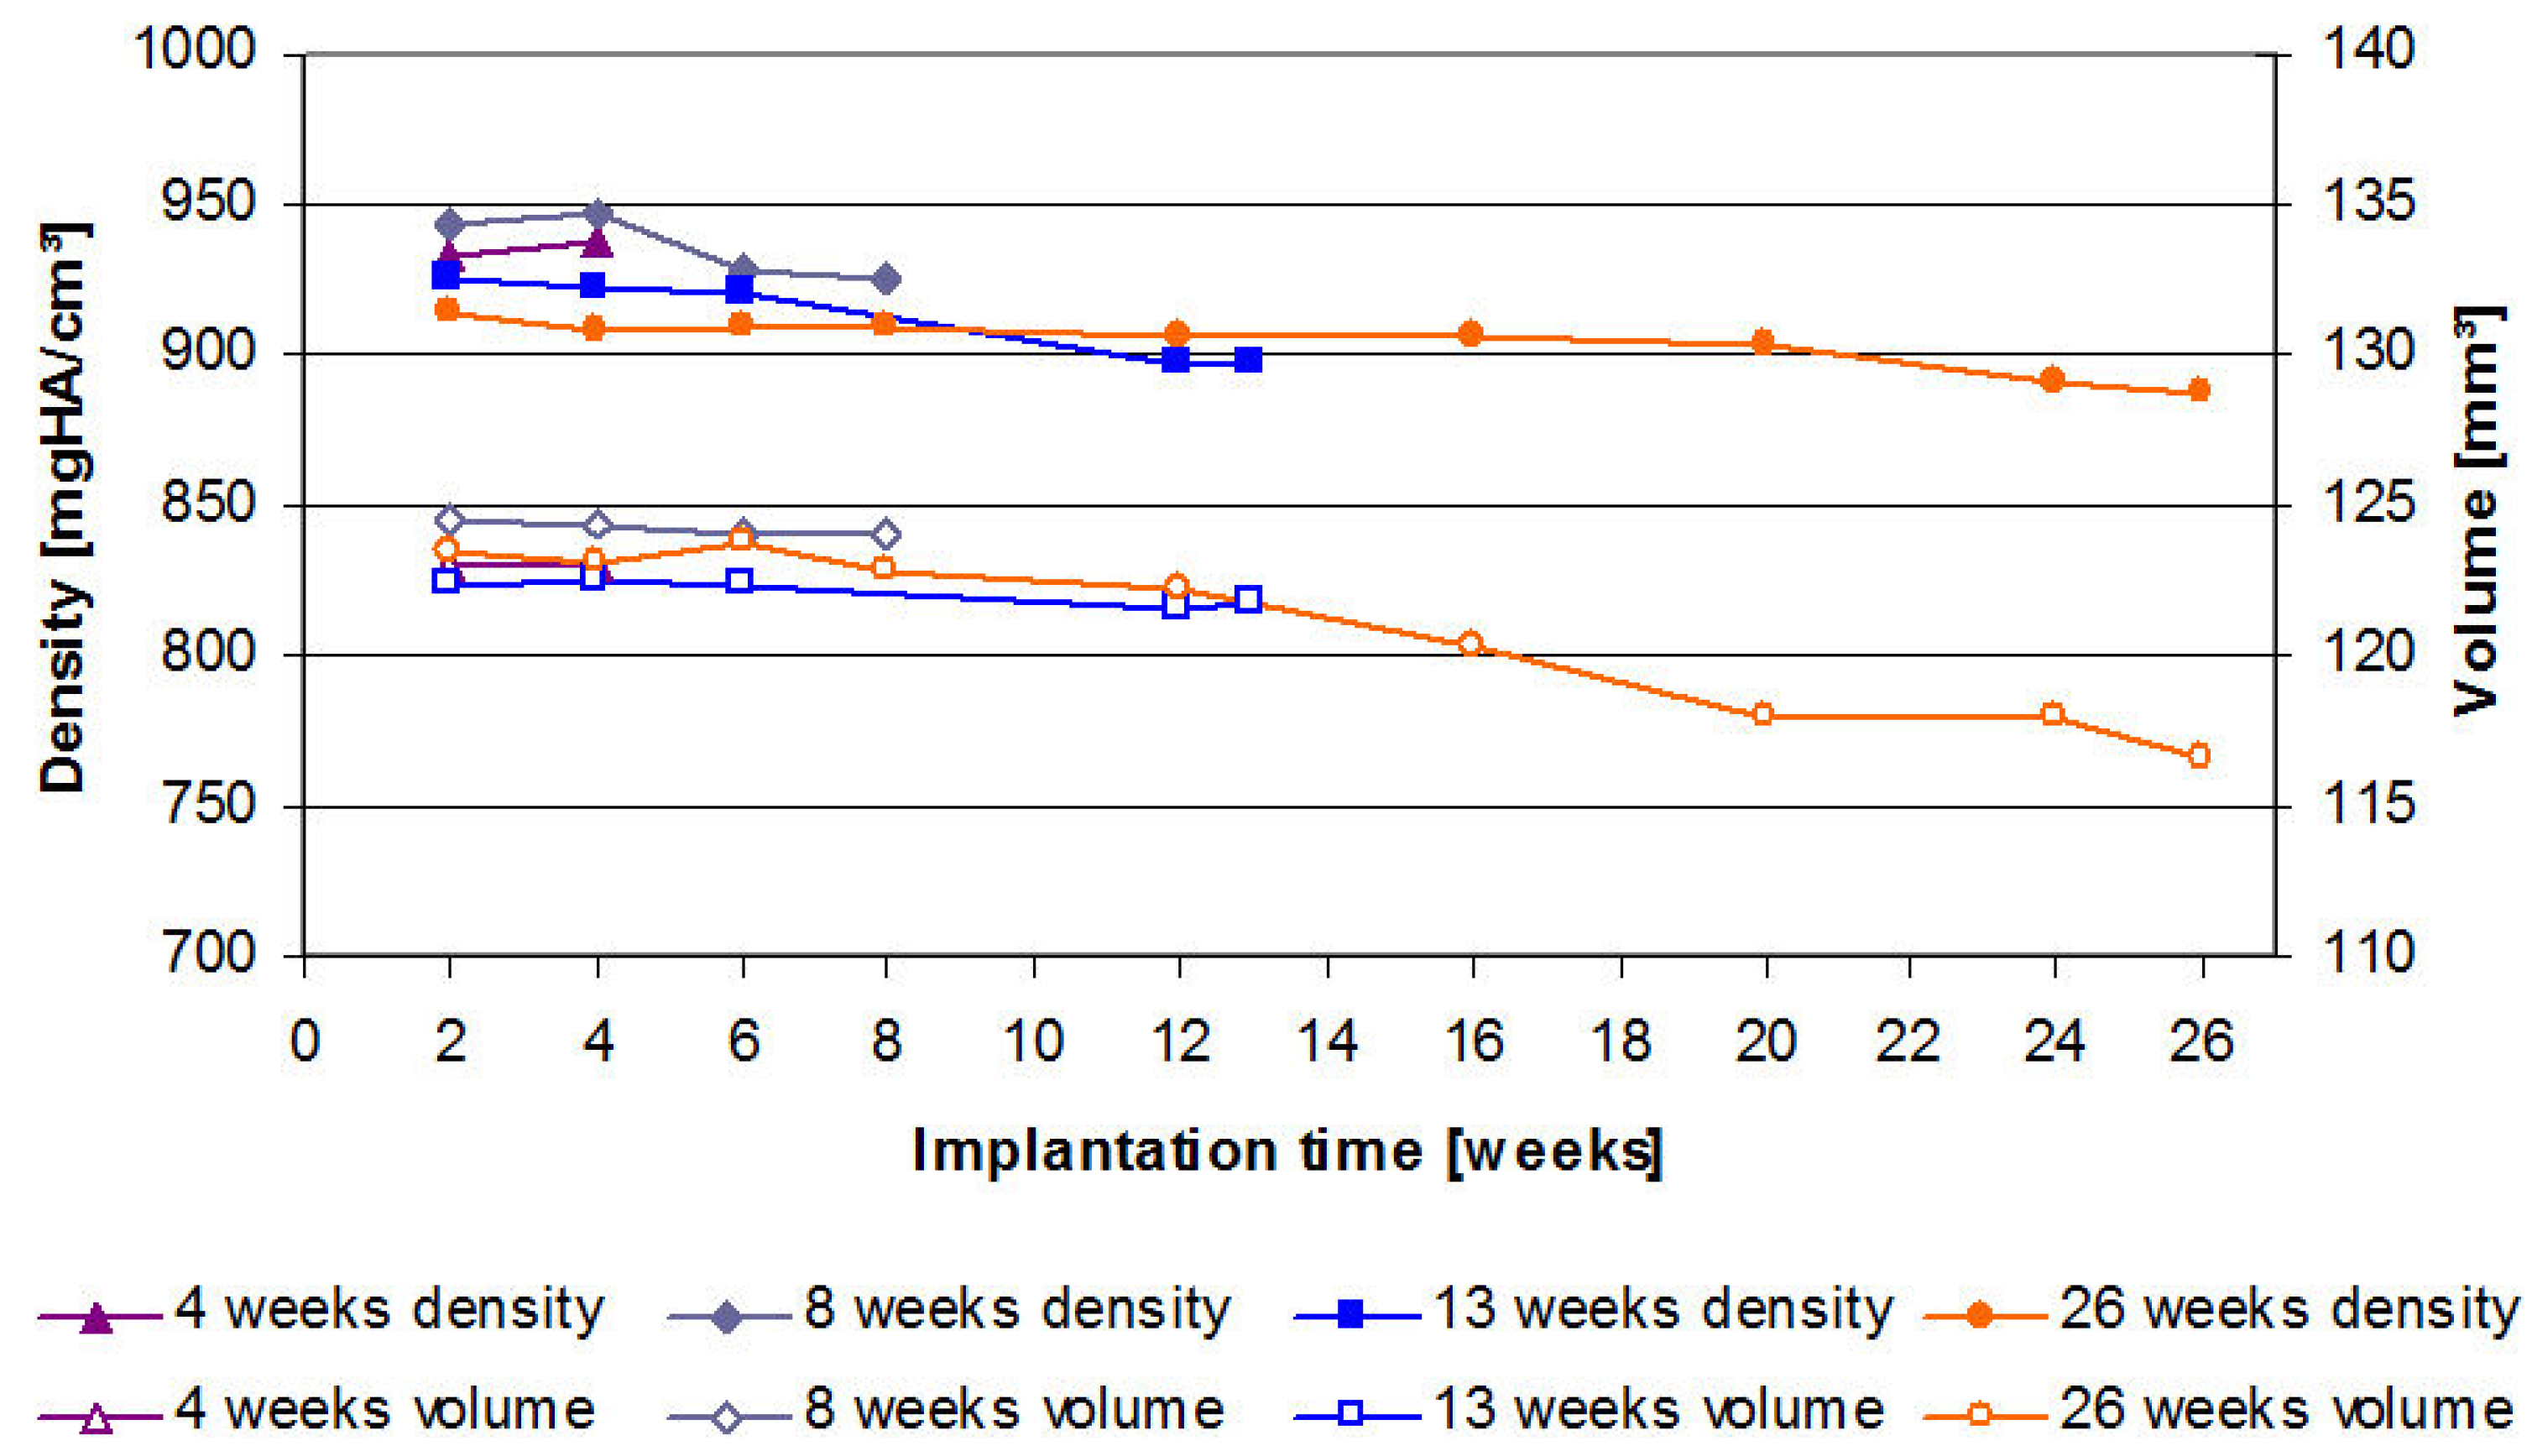

2.3. µ-Computed Tomographic Investigation of the in Vivo LANd442-Pins

3.2.5. In Vivo µ-Computed Tomography